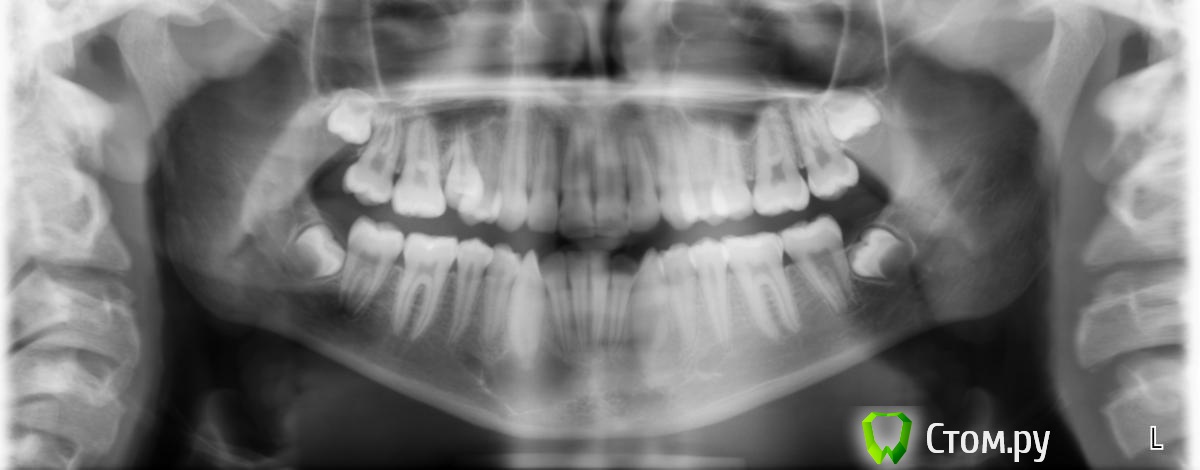

k.t.m. Опубликовано 27 сентября, 2014 Поделиться Опубликовано 27 сентября, 2014 (изменено) На кт снимке случайно обнаружили вот это образование?Ретенционная киста?Подскажите с тактикой действия, вовлечен ли корень клыка в процес,при вылущивании обязательно его депульпировать??Ребенку 14лет Изменено 27 сентября, 2014 пользователем k.t.m. Ссылка на комментарий

syrovovec Опубликовано 27 сентября, 2014 Поделиться Опубликовано 27 сентября, 2014 Может радикулярная а не ретенционная,корень кмк вовлечен Ссылка на комментарий

k.t.m. Опубликовано 27 сентября, 2014 Автор Поделиться Опубликовано 27 сентября, 2014 Да радикулярная)зуб по эод и температкрным раздражителям в норме Ссылка на комментарий

kriokov Опубликовано 27 сентября, 2014 Поделиться Опубликовано 27 сентября, 2014 Да радикулярная)зуб по эод и температкрным раздражителям в норме значит не радикулярнаякак вариант - сделать пункцию, визуально пунктат посмотреть и цитологию сделать. 2 Ссылка на комментарий

k.t.m. Опубликовано 27 сентября, 2014 Автор Поделиться Опубликовано 27 сентября, 2014 Кератокиста возможно,кто как бы поступил вылущивание или наблюдение? Ссылка на комментарий

faity Опубликовано 27 сентября, 2014 Поделиться Опубликовано 27 сентября, 2014 врядли кератокиста, лет мало пол не указан у вас, кератокиста в основном у мужчин и перегородок нет Ссылка на комментарий